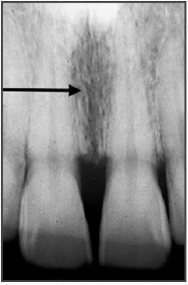

40. Which anatomical structure is indicated by the black arrow?